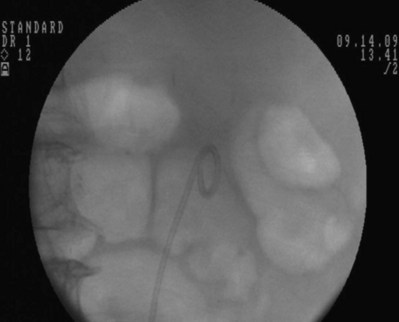

Figure 7–15 While maintaining the tip of the pusher fixed just distally to the inferior border of the pubic symphysis, the 10 portion of the dilator is removed. Asterisk shows the tip of the 10 portion.

Figure 7–16 While maintaining the pusher’s position, the guidewire is removed to form the bladder coil. Then the pusher is removed.

The ureteral stent is then advanced over the guidewire through the 10-Fr sheath by using a pusher with a small fluoroscopically visible metal band at its tip. The metal tip pusher is advanced under fluoroscopic control to the upper border of the pubic symphysis in male patients and lower border in female patients, while stabilizing the position of the lower end of the stent. The 10-Fr sheath and subsequently the guidewire are removed, allowing the stent to curl in the bladder.